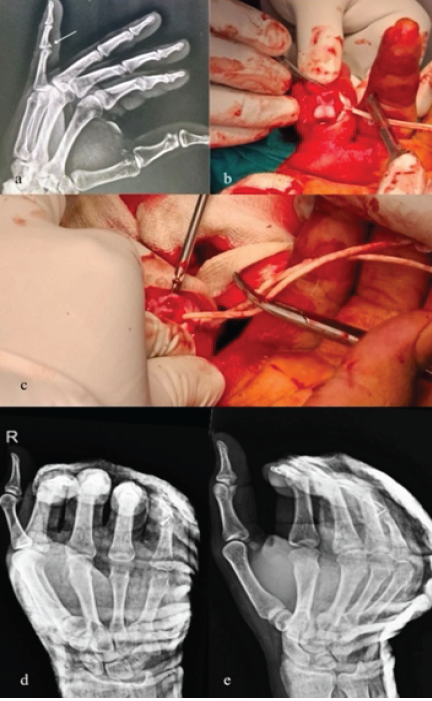

Case 5

A 30-year-old male presented 6 weeks post-injury with a volar lip fracture of the middle phalanx of the right little finger. He was managed with mini-screw fixation performed via a shotgun approach. Postoperatively, the patient was discharged with a dorsal splint applied in wrist extension with flexion at MCP, PIP, and DIP joints, allowing full flexion with an extension block for 2 weeks. After suture removal at 2 weeks, mobilization with strapping was initiated. On follow-up, the patient achieved a post-operative ROM of 0–60° at the PIP joint (Fig. 6).

Figure 6: Pre Operative Xray, Intra-Operative Clinical Pictures & Post Operative X-Rays (a) X-Ray Right little Finger Lateral View, (b) Intra-Operative Clinical Picture Showing Shotgun Approach, (c) Intra-Operative Clinical Picture Showing mini-screw fixation, (d) Post Operative X-Ray Right Hand AP View, (e) Post Operative X-Ray Right Hand Oblique View